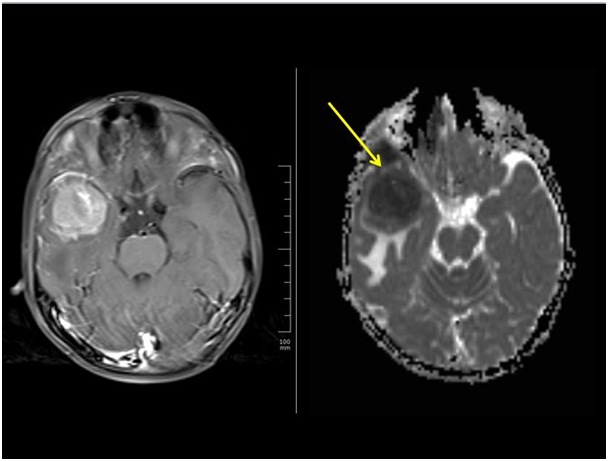

In diffusion-weighted imaging, additional gradients (which are the strong magnetic fields) are applied in very short durations. With this application, information about random molecular movements of water molecules is obtained. It is mostly used in the evaluation of strokes, since the ischemia causes restricted diffusion within the cells. However, tumors, especially cellular tumors with high nucelus/cytoplasm a ratios may also show restricted diffusion. Also, lymphomas usually show prominent restricted diffusion (Figure 2).1,2 In DTI, number of the diffusion gradient are much more than DWI. With DTI, direction of the diffusion can be measured for each voxel (smallest element of the image data), and therefore, tracts can be visualised within the brain. Presurgical evaluation of involvement or displacement of the certain tracts (such as cortico spinal tract, (Figure 3) can be shown or degree of infiltration can be estimated by measuring the diffusion parameters.

Figure 2 Lymphoma. Right temporal mass lesion. Showing intense enhancement and restricted diffusion (arrow).